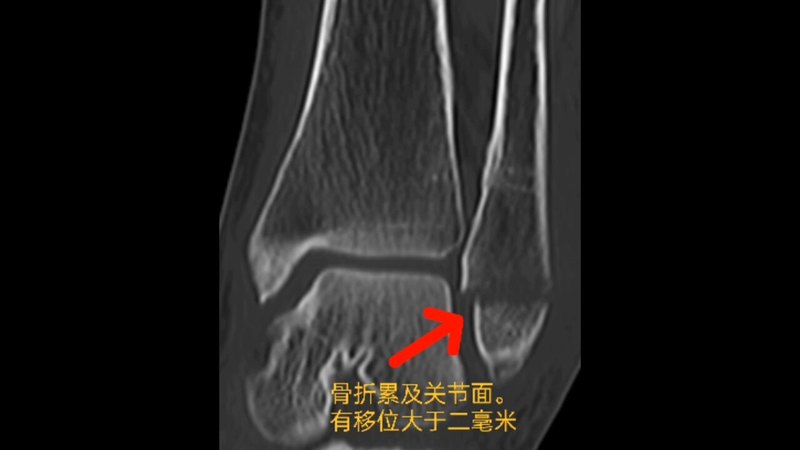

患者,女,33歲,因“騎電動(dòng)自行車車禍傷致左踝關(guān)節(jié)腫脹畸形1小時(shí)”入院,查體:內(nèi)踝前皮膚損傷(圖1),踝關(guān)節(jié)壓痛(+)。CT提示:左側(cè)內(nèi)踝骨折(圖2)。(病人車禍傷,基本醫(yī)療保險(xiǎn)不予報(bào)銷,自己購(gòu)買(mǎi)的商業(yè)保險(xiǎn)報(bào)銷)視頻1:術(shù)后3個(gè)月隨訪1.術(shù)后患者不用二次手術(shù)取內(nèi)固定物2.第二次取內(nèi)固定物的費(fèi)用與可吸收螺釘?shù)馁M(fèi)用相比,明顯少很多3.內(nèi)踝松質(zhì)骨血運(yùn)豐富,骨折愈合快,更易于可吸收螺釘?shù)氖褂?/p>